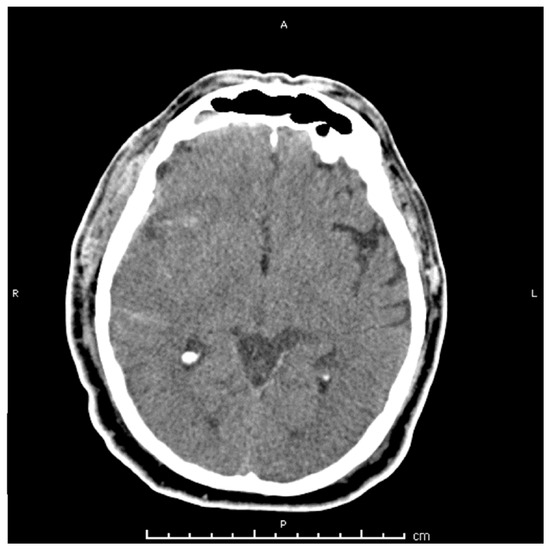

2. Case Presentation